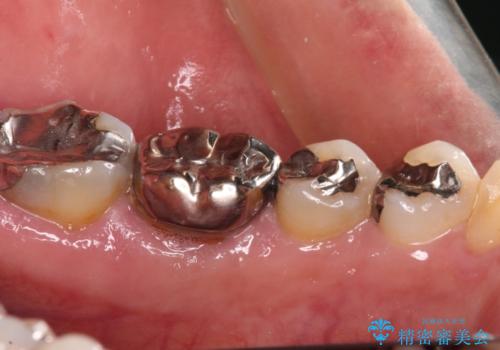

- 根っこの一部だけになった歯と咬むと痛みのある歯を気にして来院された患者様です。

上顎の歯根のみとなった歯は抜歯が必要であったので、抜歯を行い、インプラントあるいはブリッジのよる補綴治療を提案しました。

前後の歯は銀歯が装着されていたため、ブリッジによる補綴治療として、前後の歯もセラミックに置き換えることとしました。

下顎の根管治療がされた大臼歯は咬合時に痛みが認められたため、再度根管治療を行った後に補綴治療することとしました。